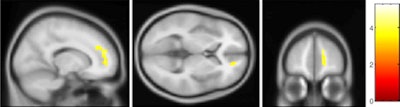

Using a voxel-based analysis, the researchers evaluated the corpus callosum, which connects the right and left hemispheres of the brain and facilitates communication between the two regions, and the right superior frontal gyrus, which coordinates an individual's sensory system and self-awareness.

They found that OCD patients demonstrated significantly increased fractional anisotropy in the corpus callosum and in the white matter of the right superior frontal gyrus, compared with the healthy control subjects.

| Parametric maps superimposed on 3D T1-weighted images show that OCD patients had significantly increased fractional anisotropy in the corpus callosum (above) and right superior frontal gyrus (below). Images courtesy of Radiology. |

The mean fractional anisotropy for the corpus callosum in the OCD group was 0.499 ± 0.038, compared with 0.446 ± 0.039 in the control group. For the white matter of the right superior frontal gyrus, the mean fractional anisotropy in the OCD group was 0.411 ± 0.024, compared with 0.375 ± 0.025 among healthy subjects.

In the increased fractional anisotropy areas, axial diffusivity was greater in OCD patients compared with the control subjects, while radial diffusivity was not significantly different.